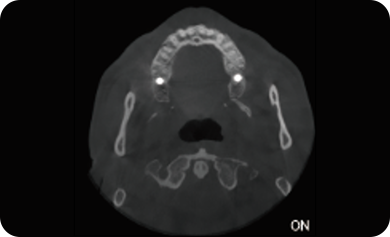

超能去伪 至臻影像

局部超清显示、 移动视野摄片

真人正侧位投影,实现CT成像区域无极可调

可根据临床需求任意调整成像区域大小实现局部超清三维显示

可根据临床需求任意调整成像区域大小实现局部超清三维显示

临床样片